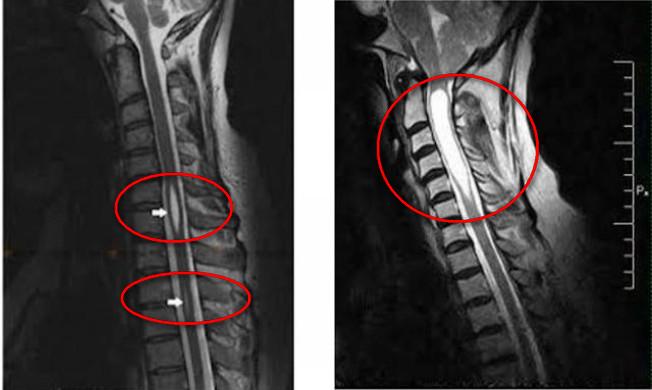

Справочно. Однако исследования Т.Мilhoratв, результаты которых были опубликованы в 2000 году, привели к изменению классификации. Она основана на данных инструментальных (МРТ) и морфологических исследований.

- магнитно-резонансная томография;